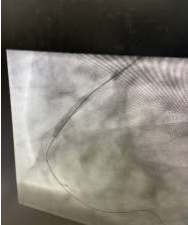

60 year old male known diabetic, hypertensive and dyslipidaemic presented with unstable angina, Coronary angiogram revealed Mid RCA pre crux lesion of 80-90% stenosis and PDA and PLV arising from Mid RCA (Fig 1). It was an angulated bend post bifurcation and hence Fielder FC wire support was taken to easily manipulate the vascular bifurcation (Fig 2) and successful PTCA+ stent to Mid RCA was done with 3x24mm Yukon choice flex stent (Fig 3& 4). TIMI III flow was achieved and post procedure period was uneventful.

FIG 2: Successful manoeuvring of Fielder FC through the bifurcation to PLV